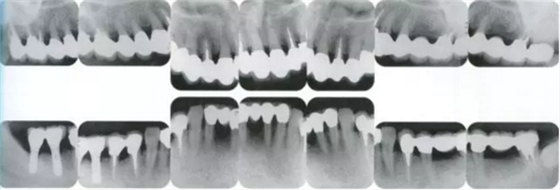

▲圖19-8,9

▲圖19-8 佩戴臨時修復(fù)體。即使在這個狀態(tài)下,依然有牙周袋殘留。

▲圖19-9 完成牙周外科治療后的狀態(tài)。

▲圖19-10,11

▲圖19-10 牙周外科治療后3周的狀態(tài)。從照片可見牙周袋的去除量。

▲圖19-11 數(shù)月以后,對臨時修復(fù)體進(jìn)行修整后的狀態(tài)。